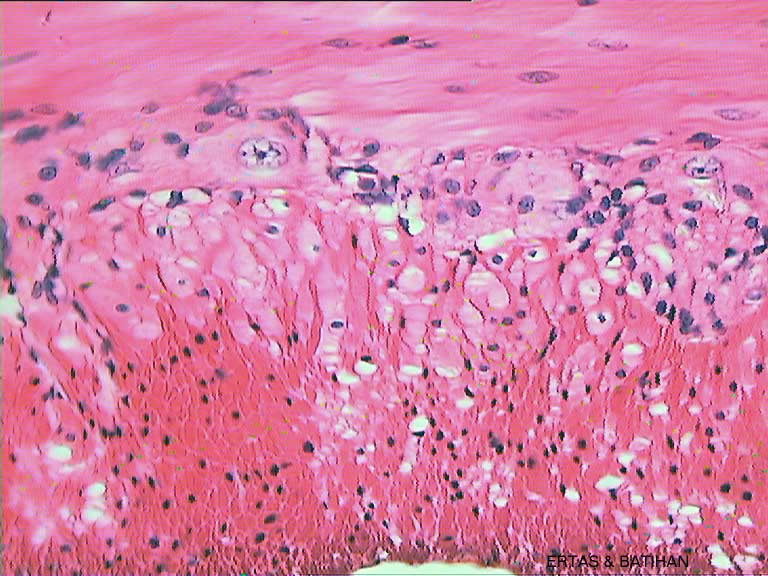

ı/Smooth-muscles-11-(40)(Duuz-.jpg